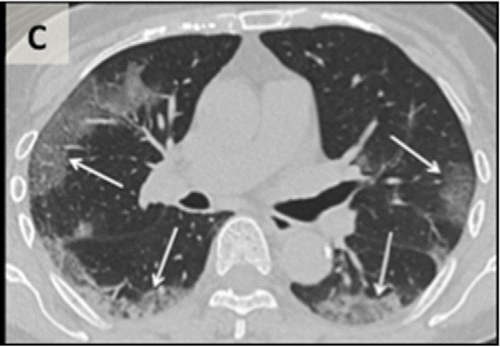

Figure 1a: An axial CT image obtained without intravenous contrast in a 36‐year‐old male (Panel A) shows bilateral ground‐glass opacities in the upper lobes with a rounded morphology (arrows). An axial CT image obtained in a 44‐year‐old male (Panel B) shows larger groundglass opacities in the bilateral lower lobes with a rounded morphology (arrows). An axial CT image obtained in a 65‐year‐old female (Panel C) shows bilateral ground‐glass and consolidative opacities with a striking peripheral distribution.

Figure 1c: An axial CT image obtained without intravenous contrast in a 36‐year‐old male (Panel A) shows bilateral ground‐glass opacities in the upper lobes with a rounded morphology (arrows). An axial CT image obtained in a 44‐year‐old male (Panel B) shows larger groundglass opacities in the bilateral lower lobes with a rounded morphology (arrows). An axial CT image obtained in a 65‐year‐old female (Panel C) shows bilateral ground‐glass and consolidative opacities with a striking peripheral distribution.